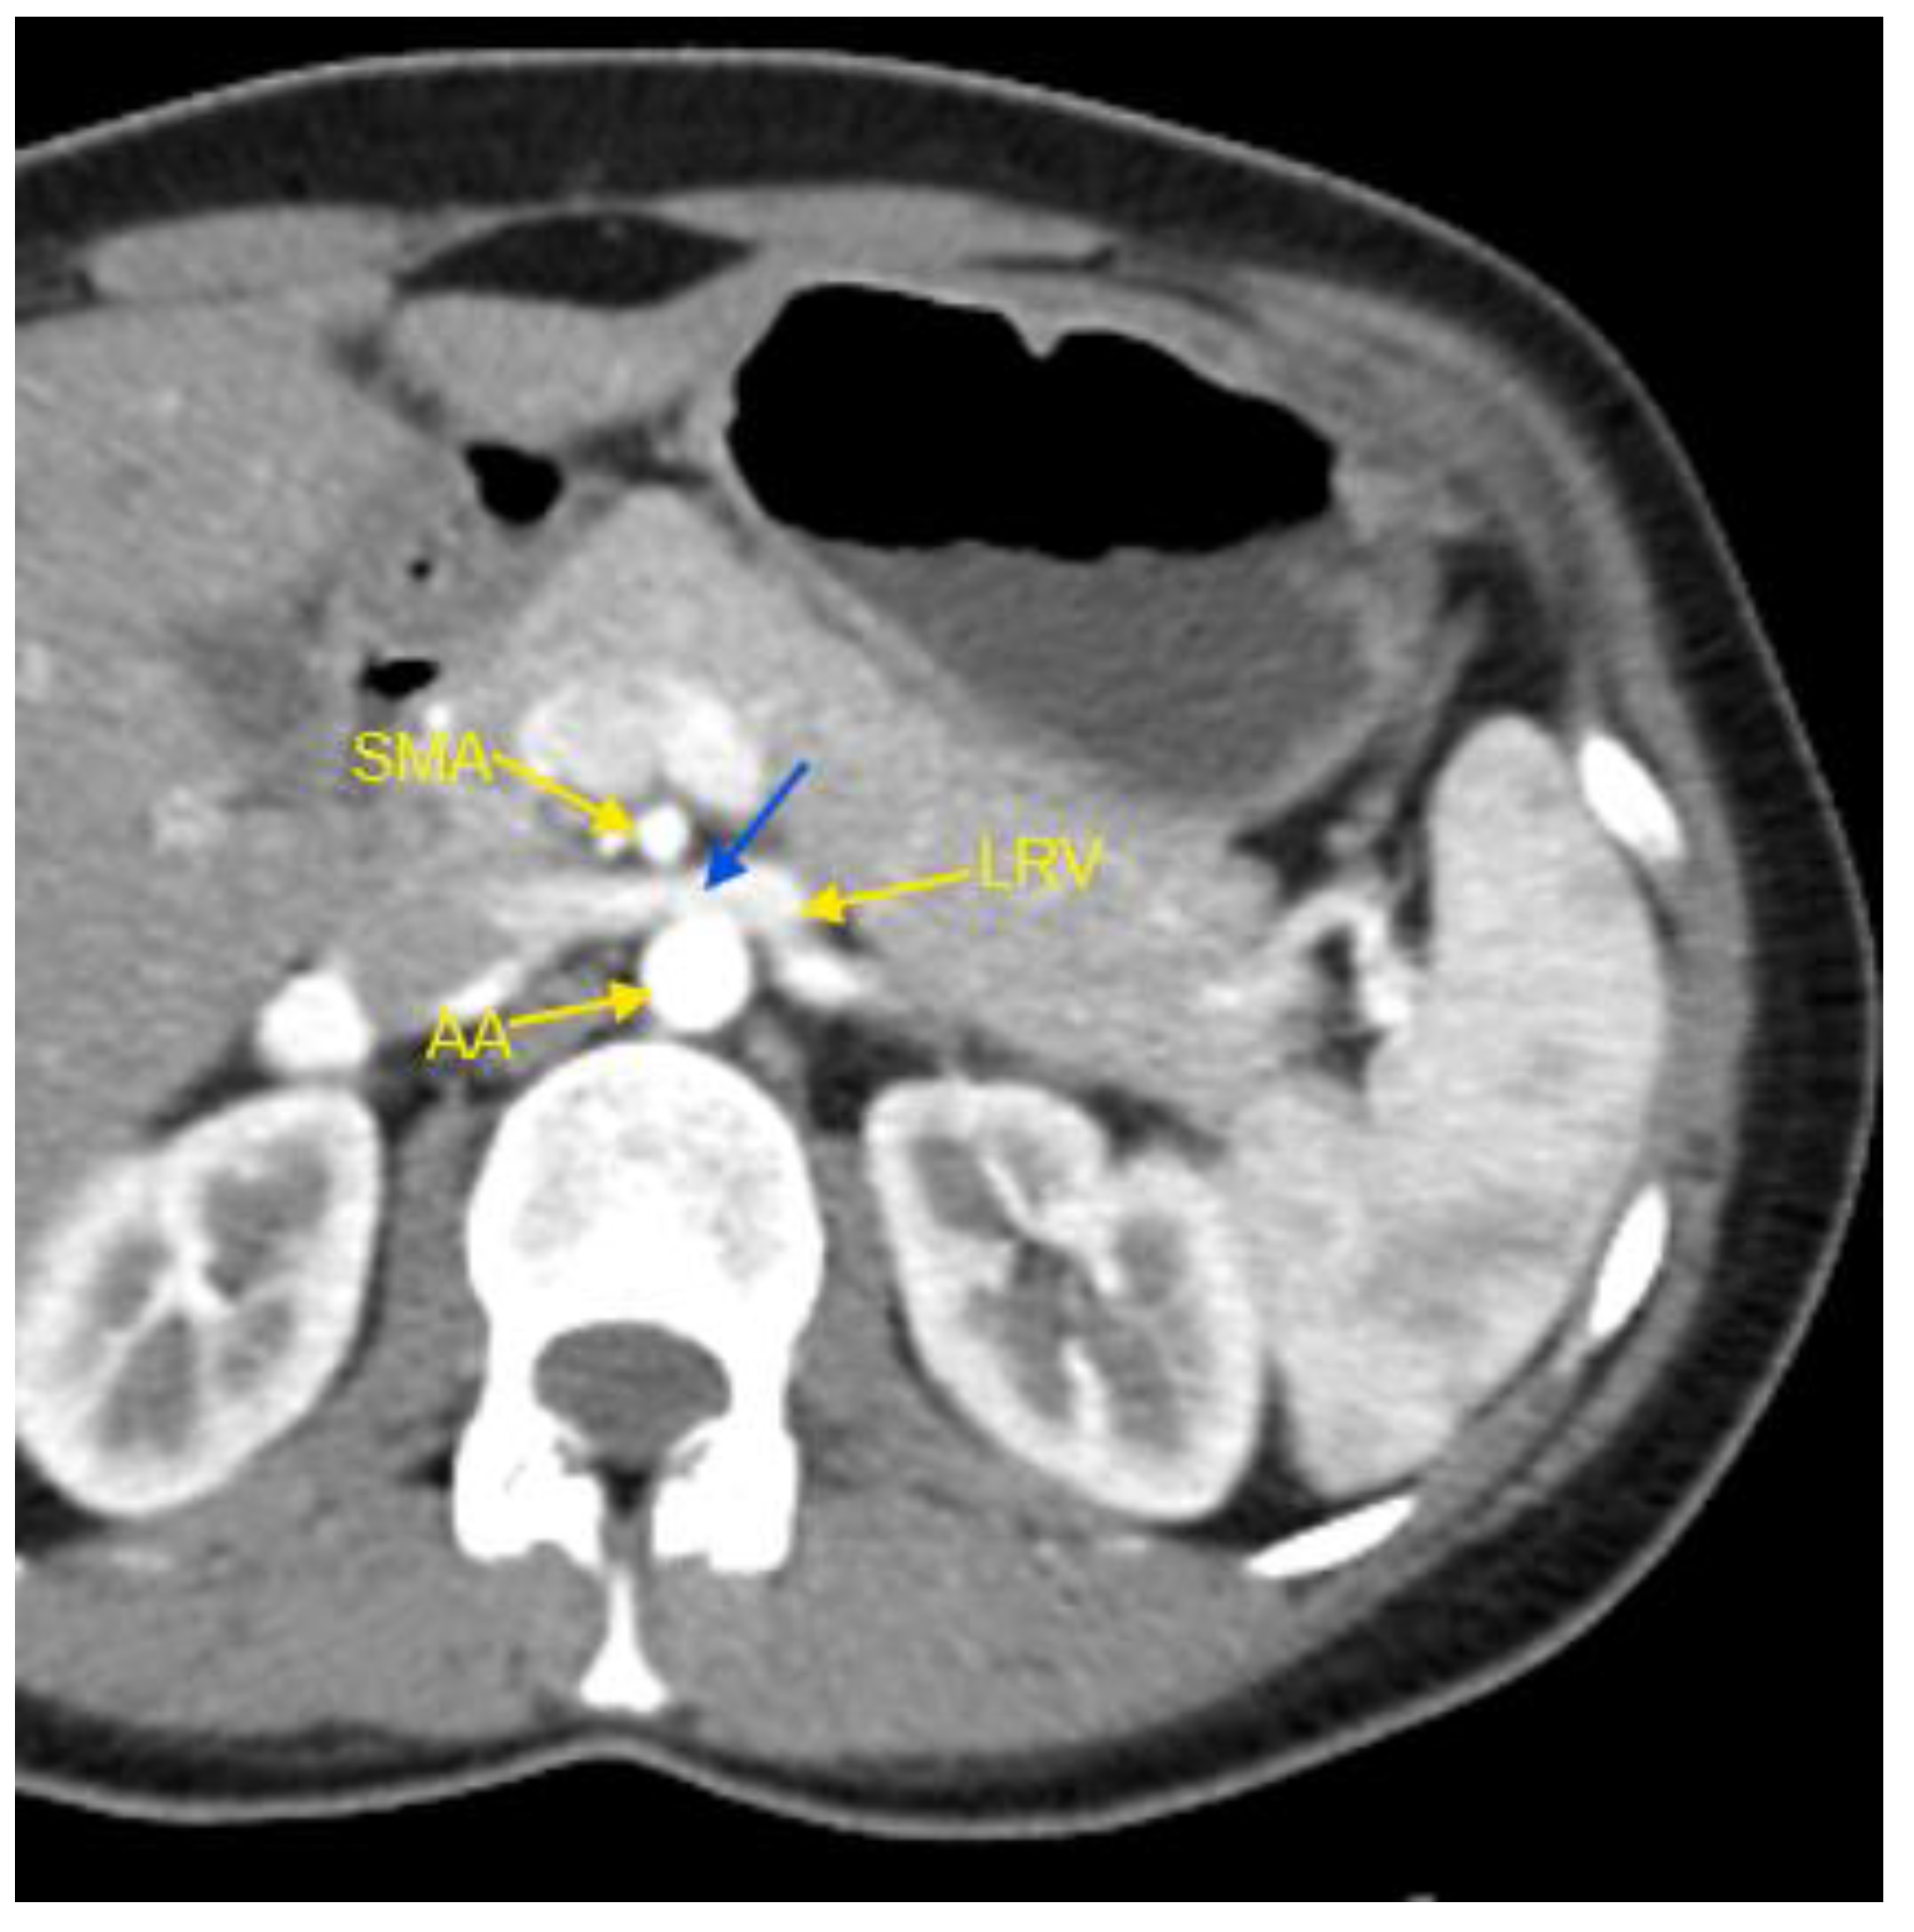

Figure 1. Contrast-enhanced CT imaging of a 44-year-old female patient, hospitalized for HTN refractory to treatment, revealed characteristic findings consistent with classic Nutcracker syndrome. The patient had been receiving a triple combination therapy comprising an angiotensin II receptor blocker (valsartan), a dihydropyridine calcium channel blocker (lercanidipine), and a thiazide-like diuretic (indapamide) at standard doses, with limited efficacy. In the accompanying image, the abdominal aorta, the superior mesenteric artery, and the left renal vein are indicated by yellow arrows. The compressed segment of the left renal vein is highlighted by a blue arrow. AA – abdominal aorta; CT – computed tomography; HTN – arterial hypertension; LVR – left renal vein; SMA – superior mesenteric artery.